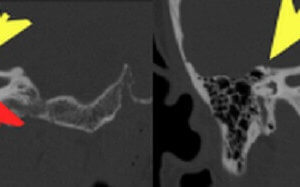

Semicircular Canal Dehiscence

There are three semicircular canals – superior, lateral and posterior. The semicircular canals are integral to maintaining balance and equilibrium with changes in body and head position. Dehiscence of the superior semicircular... Read more »